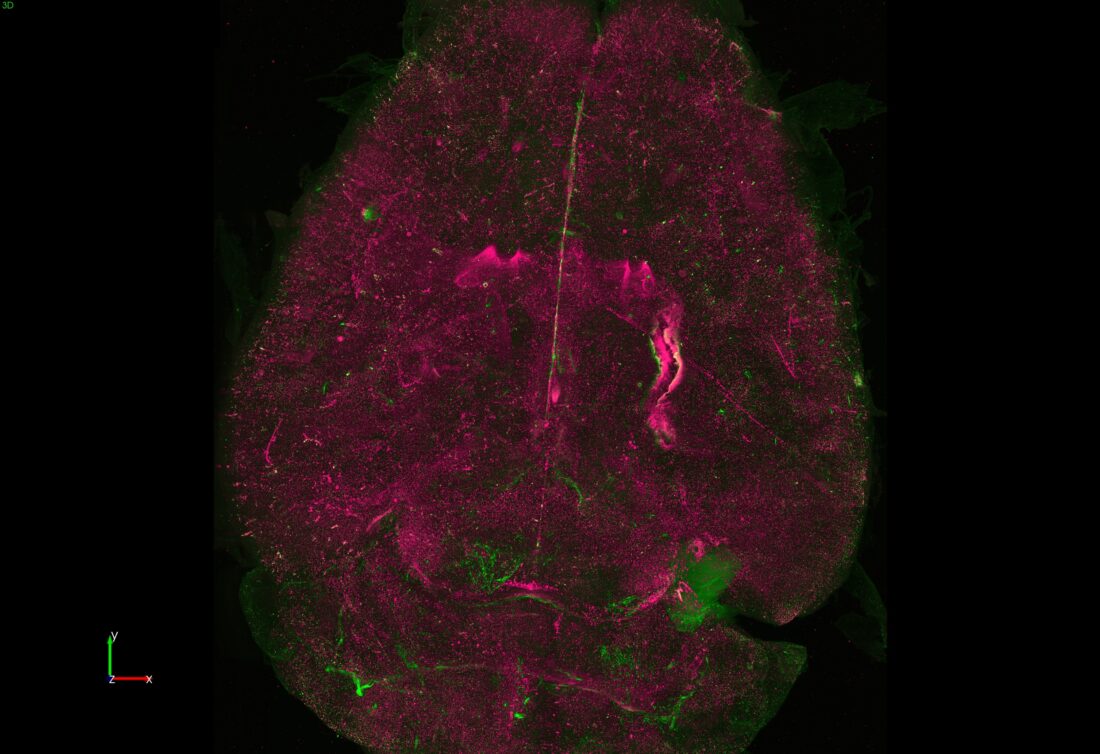

Title: EcoHIV Distribution in Mouse Brain

Description: Whole-brain imaging using an innovative light-sheet microscopy (SLICE) system was applied to visualize the timeline of EcoHIV distribution and the colocalization of NLRP3 inflammasome activation in the mouse brain.